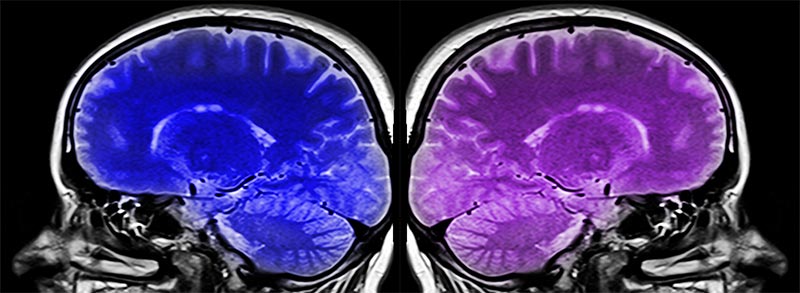

MRI Brain scans